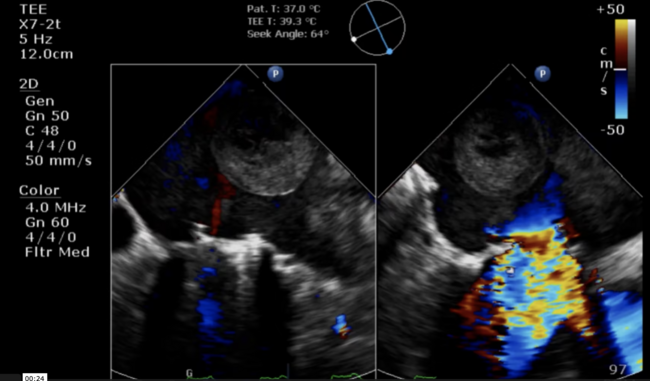

A 69-year-old woman with atrial fibrillation and rheumatic heart disease who underwent mechanical mitral replacement 20 years ago presented with sudden coma. She took warfarin regularly until 10 days prior when she developed gum bleeding. The neurologic examination revealed reduced muscle strength on the right side of the body and alteplase was administered. Then, computed tomography revealed multifocal hypodensities in the bilateral cerebellum, thalami, left parietal, and occipital lobes with thalamic hemorrhage. Anticoagulation was not given for 2 weeks until transesophageal echocardiographic examination revealed normally functioning mechanical mitral prosthesis and a 4 cm left atrial heterogenous thrombus moving around the left atrium like a ping pong ball. Also visible was a thrombus within the left atrial appendage (Figure 1A and 1C, arrow). The left atrial thrombus moved toward the mitral orifice and was bounced away by mitral regurgitant jet; it moved like a ping pong ball (Video Series). Cardiac arrest occurred 1 week after examination with successful resuscitation, presumably due to transient mitral obstruction of the huge thrombus. Her condition gradually recovered and anticoagulation has been resumed.